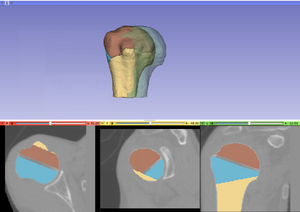

Tutorial and description of panelsUsing the first tab of the loadable module the user should provide the following input data: -3D CT image(volume) of non fractured bone (='Reference image') After providing the input data the 'Initialize reconstruction'-button should be pressed in order to create 3D models of the labelmaps and initialize the reconstruction process If the user wants to provide a better manual interaction the transform sliders (from within the fracture reconstruction) module can be used. Better initialization will decrease the calculation times for the subsequent alignment process and potentially lead to better results. The "Reset manual transform" button to reset the postion of each fragment to the state prior to the manual interaction. After the initialization process is finished the second tab will be opened. The 2D and 3D views will be updated and a surface rendering of the fragments and reference bone will be provided. The user can change colors, opacity and visibility for each single fragment.

After the first step of the reconstruction is finished and user can inspect the intermediate result. 2D and 3D views will be update according to the calculated transformations. At this point the user, the following scenarios are possible: 1) Good registration - Accept registration without performing further registration (fine tuning part will be skipped). By pressing the "Start fine tuning" button the second part of the reconstruction process in which the fragments will be aligned against each other (without using the reference bone) will be started. The parameters for this step can be changed in the corresponding parameter tab ("Parameters for fine tuning") After the calculations for the fine tuning step are finished, the last tab will be opened ("Result step 2"). Again 2D and 3D views will be updated accordingly and the same 4 scenarios as in the previous step are possible.  Updated 2D and 3D views after final step of reconstruction. Note that the visible gaps are due to missing bone that has been "simulated" in this (toy) example. This view was generated using a wireframe representatioin of the fragments in combination with a volume rendering of CT dataset of the (healthy) reference bone